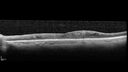

Elmiron (pentasosan polysulfate) Macular Toxicity104 views77 year old female who had been on Elmiron for 20 years and stopped it 2 years agoMar 15, 2026

Elmiron (pentasosan polysulfate) Macular Toxicity89 views77 year old female who had been on Elmiron for 20 years and stopped it 2 years agoMar 15, 2026

Elmiron (pentasosan polysulfate) Macular Toxicity35 views77 year old female who had been on Elmiron for 20 years and stopped it 2 years agoMar 15, 2026

Elmiron (pentasosan polysulfate) Macular Toxicity41 views77 year old female who had been on Elmiron for 20 years and stopped it 2 years agoMar 15, 2026

Elmiron (pentasosan polysulfate) Macular Toxicity45 views77 year old female who had been on Elmiron for 20 years and stopped it 2 years agoMar 15, 2026

Elmiron (pentasosan polysulfate) Macular Toxicity46 views77 year old female who had been on Elmiron for 20 years and stopped it 2 years agoMar 15, 2026

Elmiron (pentasosan polysulfate) Macular Toxicity38 views77 year old female who had been on Elmiron for 20 years and stopped it 2 years agoMar 15, 2026

Elmiron (pentasosan polysulfate) Macular Toxicity37 views77 year old female who had been on Elmiron for 20 years and stopped it 2 years agoMar 15, 2026

Elmiron (pentasosan polysulfate) Macular Toxicity36 views77 year old female who had been on Elmiron for 20 years and stopped it 2 years agoMar 15, 2026

Elmiron (pentasosan polysulfate) Macular Toxicity40 views77 year old female who had been on Elmiron for 20 years and stopped it 2 years agoMar 15, 2026